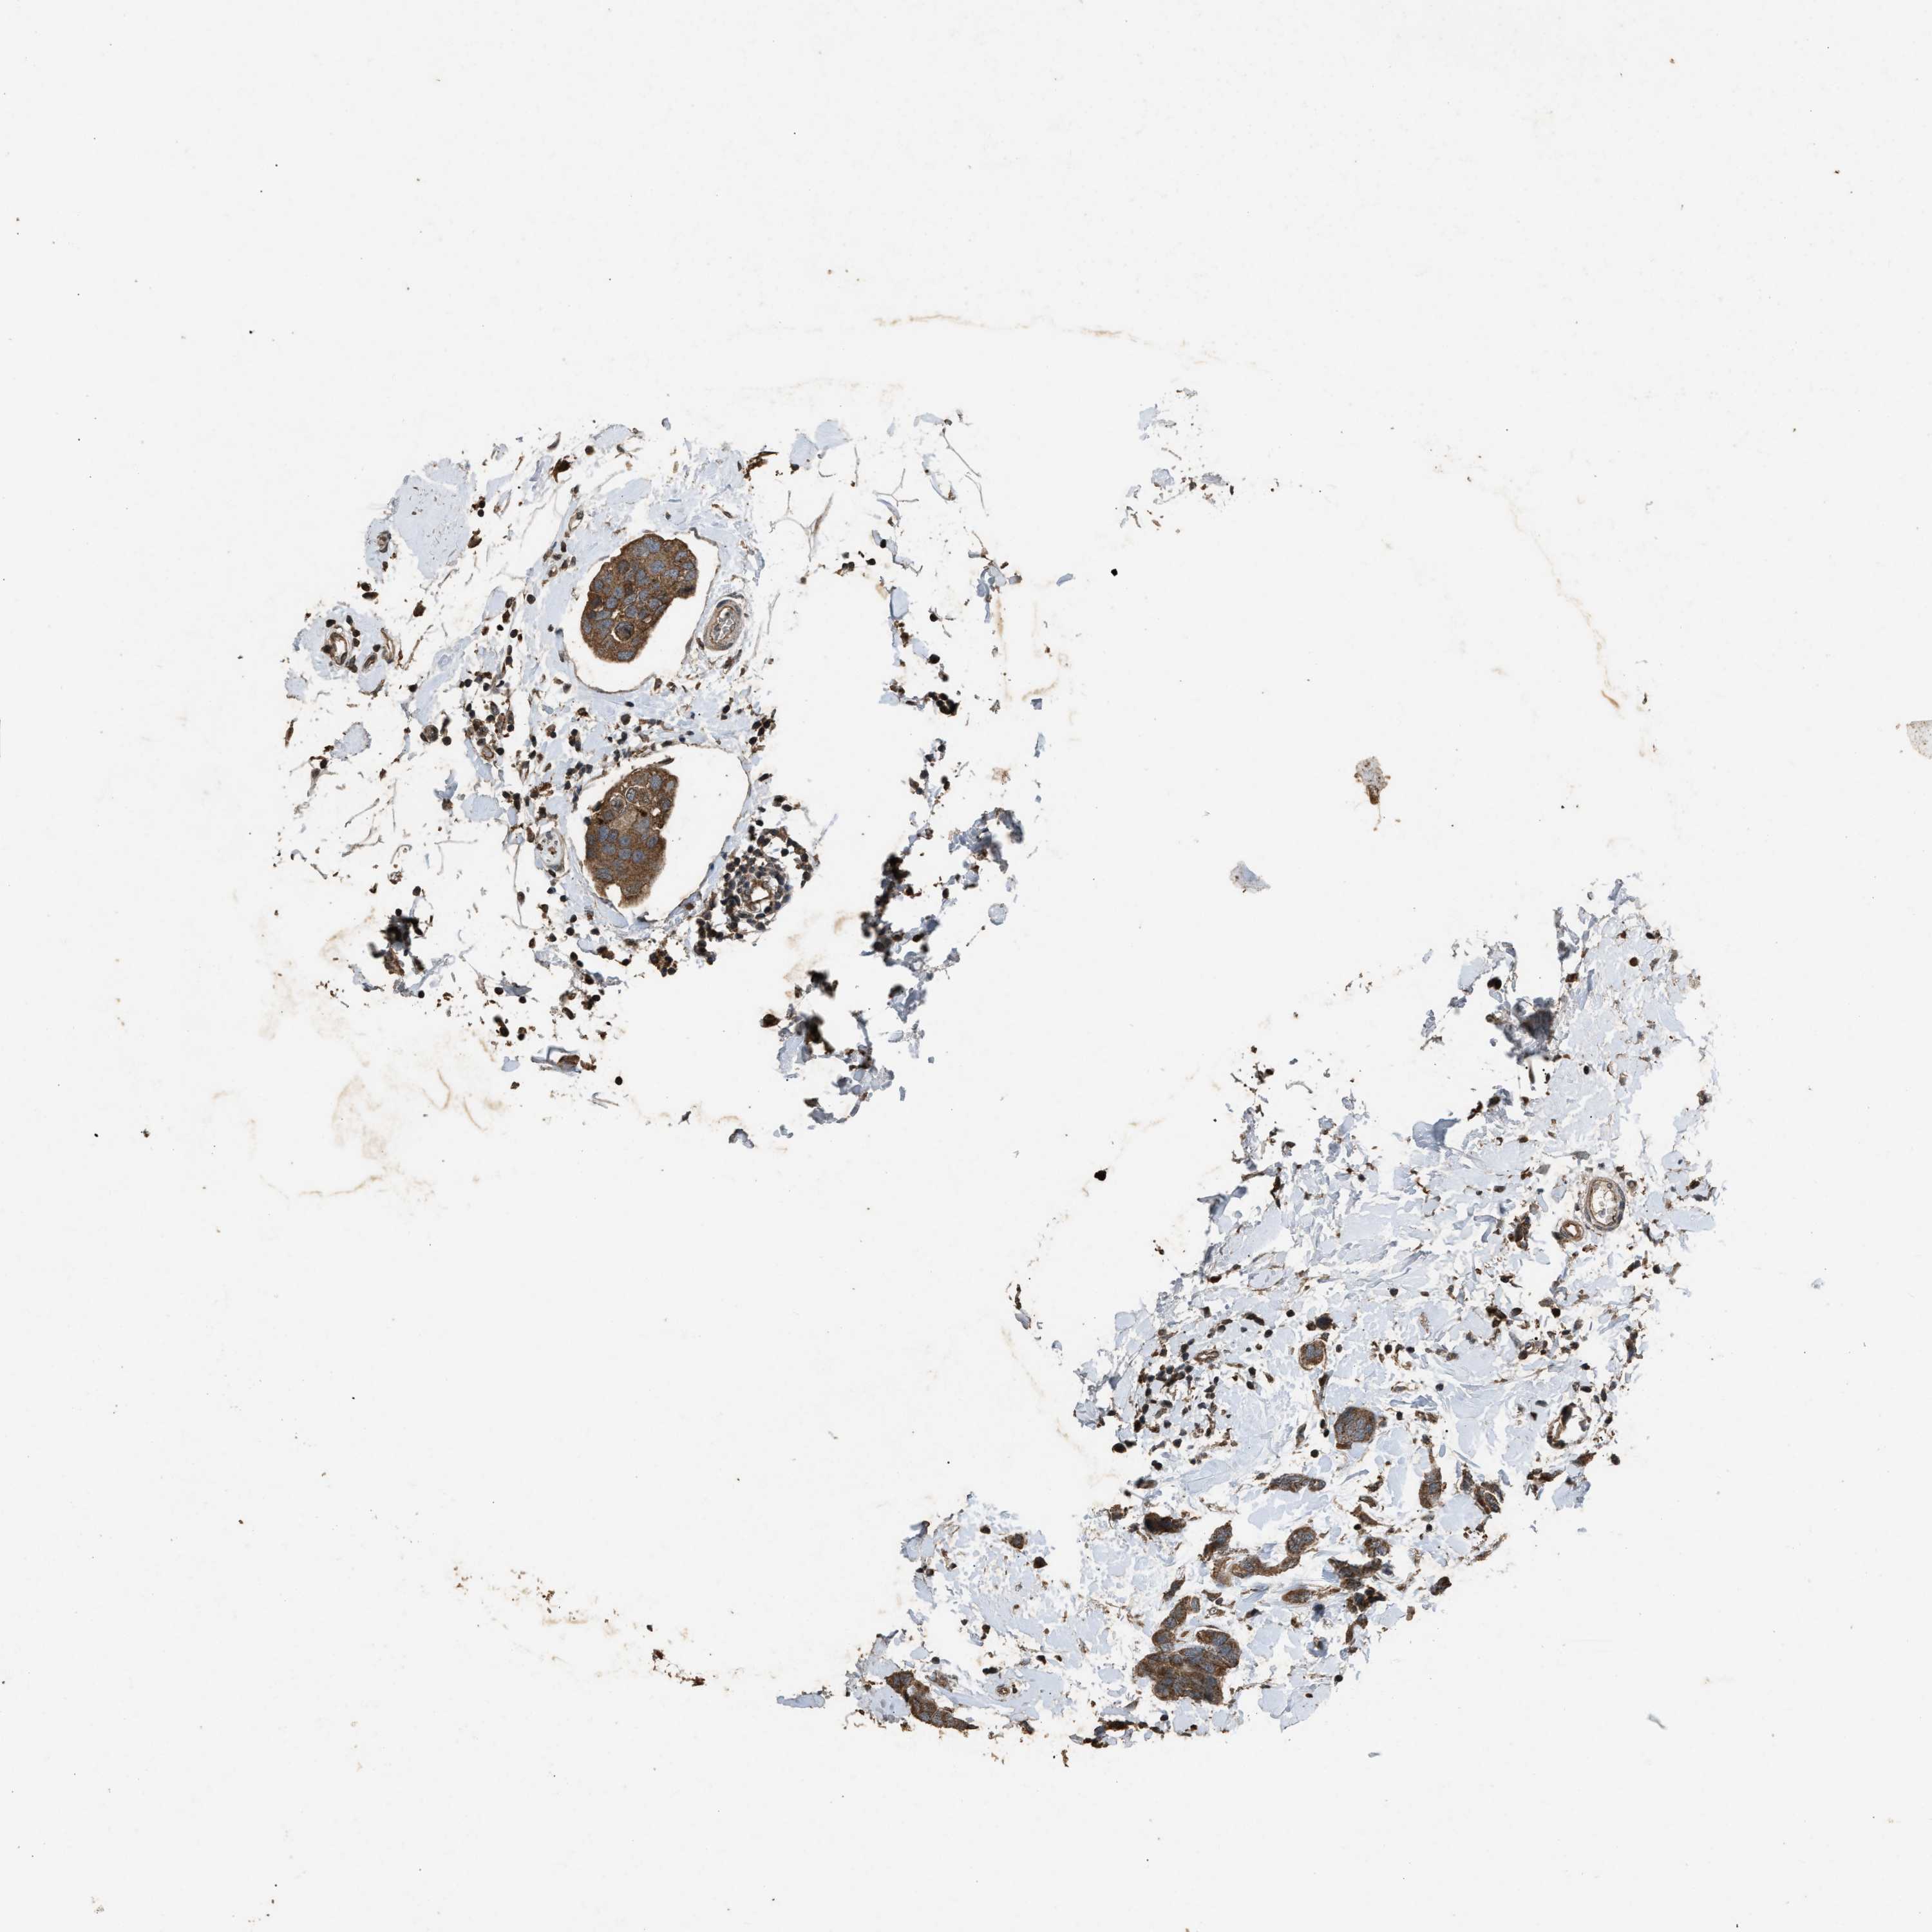

CANCER BREAST CANCER Show tissue menu

BRCA TCGA BRCA VALIDATION PROTEIN EXPRESSION